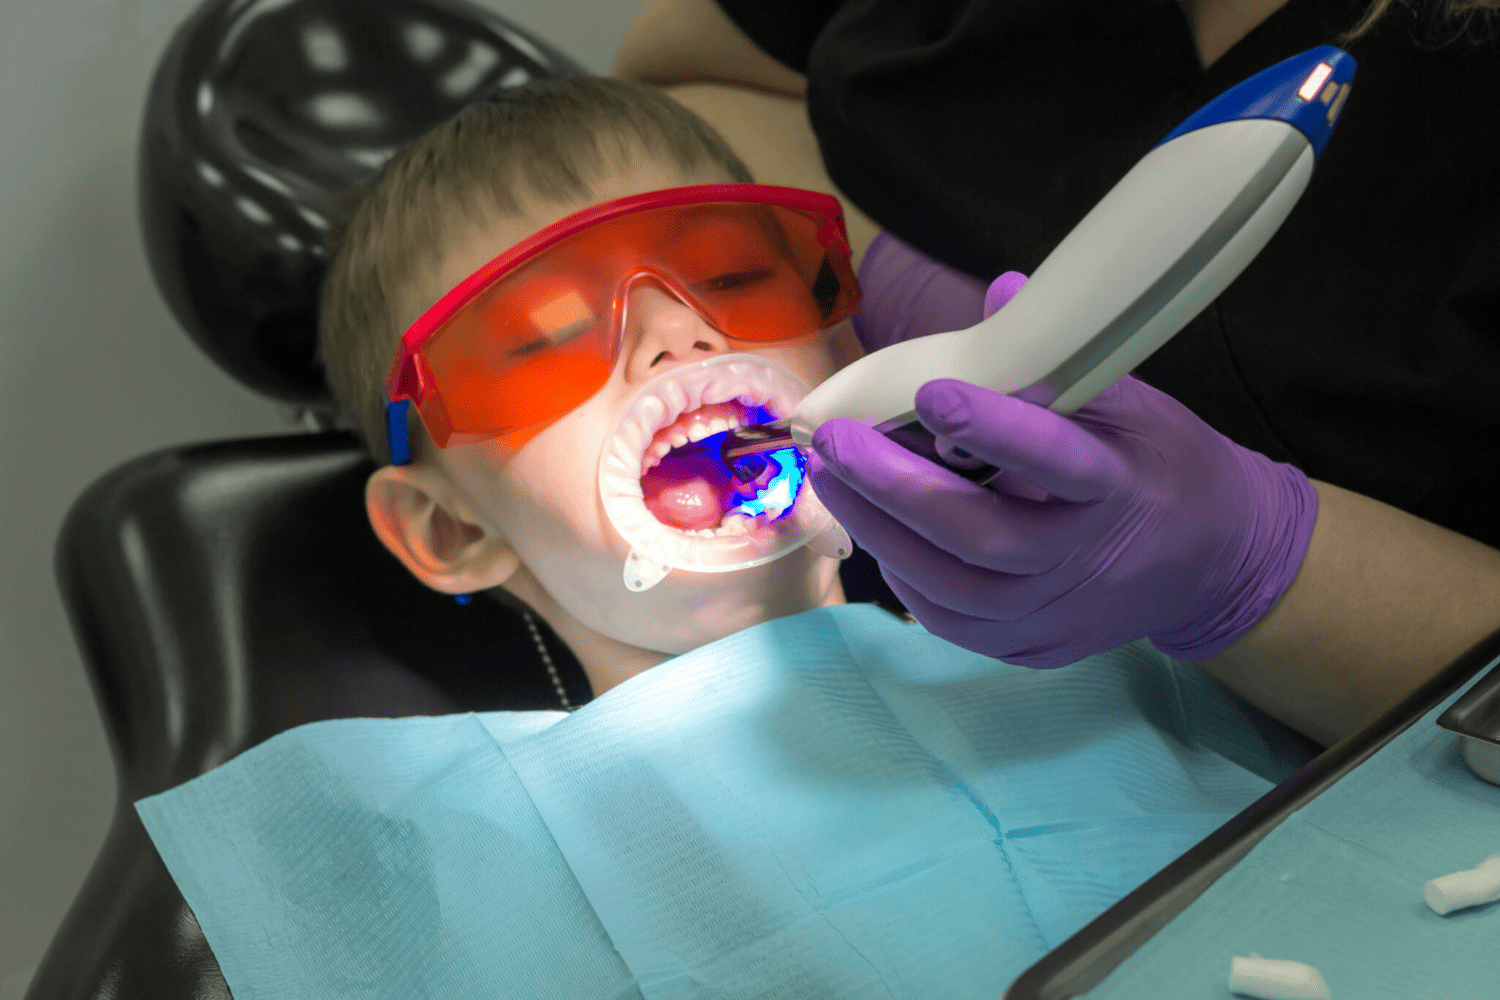

READ MOREKids Dentistry Services Crowns Bridges Dentures Teeth Cleaning...